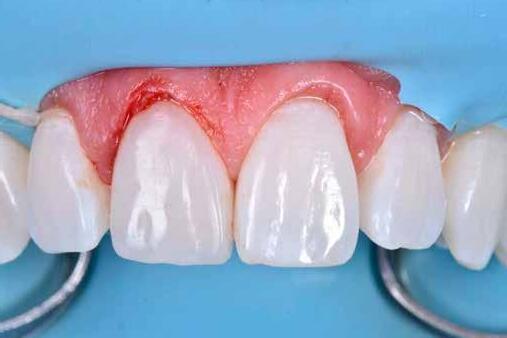

Egy 30 éves, negatív kórtörténettel rendelkező beteg azzal a kéréssel fordult hozzánk, hogy cseréljük ki az UR1 traumája után, 10 évvel korábban készült korábbi kompozit-helyreállítást.

A klinikai vizsgálat során az UR1 reagál a viabilitási tesztre, és az ugyanazon a napon készült röntgenfelvételen nem mutat periapikális elváltozásokat (1. ábra).

Az UR1 elszíneződött, és palatálisabb helyzetben van, mint az ellenoldali központi UL1 (2. ábra)

Az esztétikai elemzés a gingivális zenit aszimmetriáját mutatja az UR1 és az UL1 között. Parodontális szonda segítségével, plexusérzéstelenítés után, az IA

típusú funkcionális hám megváltozott passzív erupcióját igazoljuk Coslet és mtsai. osztályozása szerint (3. ábra)

A lehető legkonzervatívabb helyreállító kezelés elvégzése érdekében a páciensnél, figyelembe véve a megtartott fogelem korát és vitalitását, a tervezés és a diagnosztikai felviaszolás után a közvetlen kompozit-helyreállítás elvégzése mellett döntünk.

A kezelés napján, helyi plexusérzéstelenítést követően, az UR1-et kofferdámmal izoláljuk, kiterjesztve az izolációt az első premolárisokra (4. ábra)

Ezt követően eltávolítjuk a törött kompozt-helyreállítást, és az előkészített fogon rövid ferdére preparálást készítünk, majd az UR1 teljes felületén homokfúvást végzünk 27 μm-es alumínium-oxid porral (5. ábra)

A megváltozott passzív erupció korrigálása érdekében úgy döntöttünk, hogy a fog kiemelkedési profilját a vesztibuláris kidomborodás hangsúlyozásával és az ellenoldali elemmel való szimmetriára törekvéssel újra létrehozzuk. Erre a célra

egy előre megformázott fémmatricát használunk, amelyet két ékkel blokkolunk.

A matrica adaptálása után az adhéziós eljárásokat egy 3 lépéses etch&rinse rendszerrel végezzük. Minden egyes lépést 40 másodperces, UV-fénnyel történő polimerizálás követ (6. ábra)

A vesztibuláris kiemelkedési profilt zománcszínű kompozittal (a TOKUYAMA DENTAL ESTELITE ASTERIA WE termékével) állítjuk helyre (7. ábra).

A diagnosztikai felviaszolás szilikonindexének elkészítése után a palatinális falat zománcszínű kompozittal (a TOKUYAMA DENTAL ESTELITE ASTERIA WE termékével) helyreállítjuk (8. ábra)

Ezt követően helyreállítjuk a dentin anatómiáját a mamelonok reprodukálásával egy átlátszatlan dentinszínű kompozittal (a TOKUYAMA DENTAL ESTELITE SIGMA QUICK OA2 termékével); ez a szín alapvető fontosságú lesz a diszkromatikus elem színének korrigálásához is (9. ábra) Világoskék és fehér hatású árnyalatokat (a TOKUYAMA

DENTAL ESTELITE COLOR termékét) alkalmazunk az opá-

losság emulálásához az incizális területen (10. ábra)

A rétegezést egy zománcszín (a TOKUYAMA DENTAL ESTELITE ASTERIA WE terméke) használatával végezzük a vesztibulárisban, egyszeri hozzáadással. A vesztibuláris felületet háromdimenziós térfogatban modellezzük és vezéreljük annak érdekében, hogy a lehető legkevesebb végső kiigazítás legyen. Ezután 20 másodpercig polimerizáljuk, majd 40 másodpercig polimerizáljuk vesztibulárisan és palatinálisan, miután bevontuk őket gliceringéllel a kompozit hibrid rétegének elkerülése érdekében (11. ábra).

A finírozási és polírozási eljárásokat úgy végezzük, hogy megpróbáljuk emulálni az UL1 átmenő vonalait (12–13. ábra)

A pácienst 21 nap (14–15. ábrák) és 12 hónap (16. ábra) után ismét ellenőrizzük, hogy értékeljük az esztétikai eredményt a forma és a szín tekintetében.